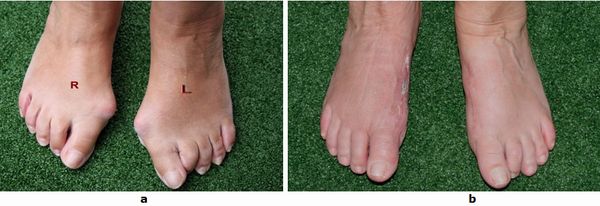

Der schmerzhafte Kleinzehenballen ist eine nicht seltene Begleiterkrankung des Hallux valgus und kommt häufig kombiniert mit einem Spreizfuß vor. Die Prominenz des fünften Mittelfußköpfchens führt zu Druckbeschwerden im Schuh aus denen eine schmerzhafte Behinderung beim Gehen resultieren kann. Breites Schuhwerk und spezielle Polster können vorübergehend die Symptome lindern. Durch eine Begradigung des fünften Mittelfußknochens kann die Fehlstellung behoben werden. Es kommen verschiedene Verfahren je nach Ausprägung der Deformität zur Anwendung.

Abb.8: Korrektur des schmerzhaften Kleinzehenballen (Schneiderballen, Taylors bunion) durch die Kombination einer basisnahen Korrektur und einer Chevronette Osteotomie.

a Fehlstellungswinkel vor der Operation.

b Die Knochenachsen sind wieder parallel und der Vorfuß verschmälert.